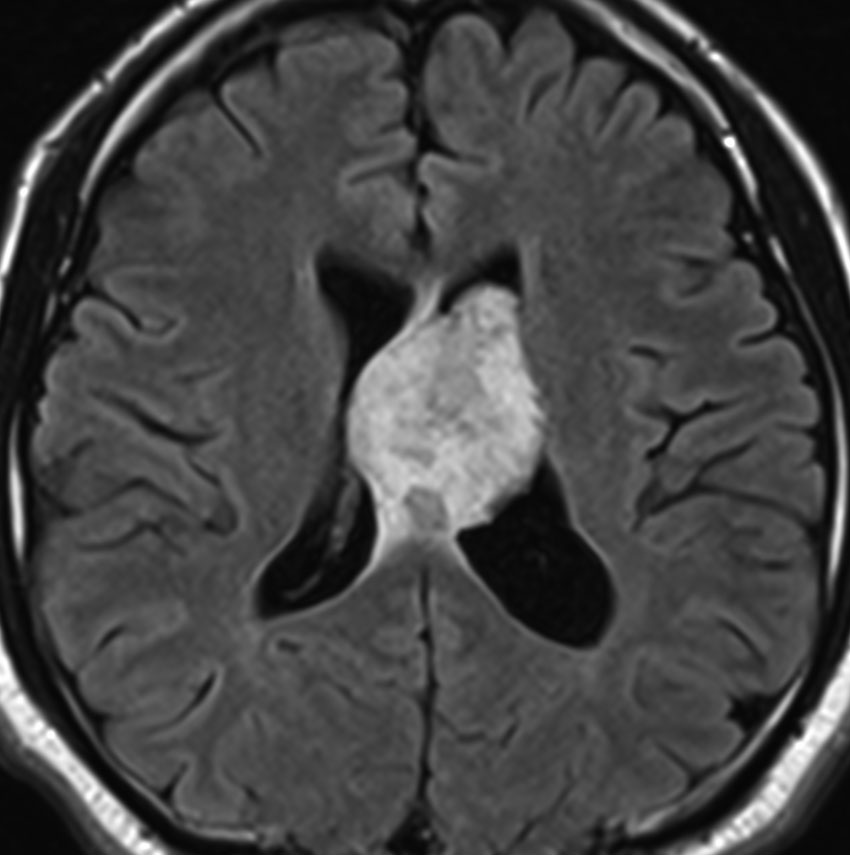

よくみつかる典型的な例です

中年男性に偶然発見された15mmくらいの上衣下腫です。側脳室前角の壁にピッタリくっつくようにキノコのように生えています。下の2枚はガドリニウム造影ですが増強されないのが特徴です。この点で中枢性神経細胞腫 central neurocytomaと区別できます。中枢性神経細胞腫はゆっくりですが大きくなる腫瘍です。でもこのような上衣下腫は大きくなるのはとてもまれです。小さいし水頭症にもならないので,なにも治療しないでほっておきます。間違っても開頭手術などしません。